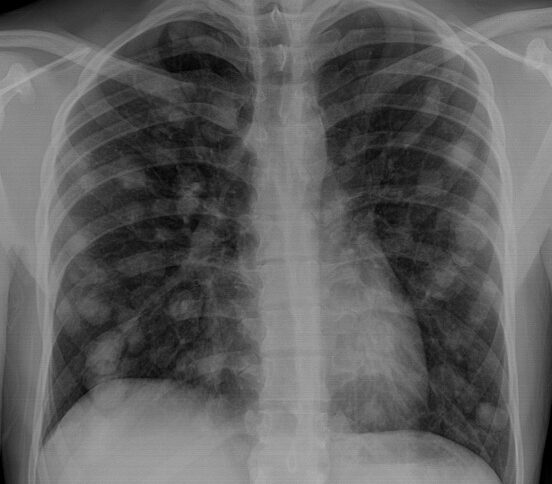

he said I counted thirty-two of them in one lung before

I quit counting them